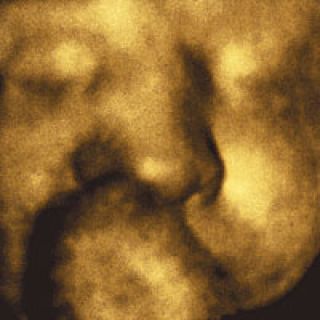

FAN › UNA FOTóGRAFA ELIGE SU IMAGEN FAVORITA: PAULA GRANDIO Y UNA IMAGEN 3D DE UN BEBé POCO ANTES DE NACER

Recuerdos del futuro

Ahora me doy cuenta: las dos imágenes que estuve considerando son un poco proféticas, muestran algo inaccesible. Este es el retrato de Dante antes de nacer.

La foto me llegó en un attachment-panza que tenía dos fotos que, me imagino, son casi simultáneas: en una está Paula, la madre, mostrando su panza feliz con el pijama de Juan –o espero que ése sea el pijama del padre...–. En el otro archivo, que se llama Bebito-foto-3Dwater.jpg., estaba Dante chupándose el dedo. Tiene los ojos cerrados; me pregunto si ya los habrá abierto o si le molestará alguna luz... ¿Cómo habrán hecho? Creo que la foto es hermosa, y como Juan no puede dejar de ser un gran fotógrafo, meticuloso, la foto está dosificada, no es tan inocente. En todo caso, después de lagrimear un poco lo llamé y me chusmeó las opiniones de las abuelas, de los tíos... naturalmente yo también quise opinar y nos ponemos a discutir, que si tenía la nariz de la madre, que a quién se parecía... y de golpe me veo opinando de alguien que no conocía, que todavía no nació...